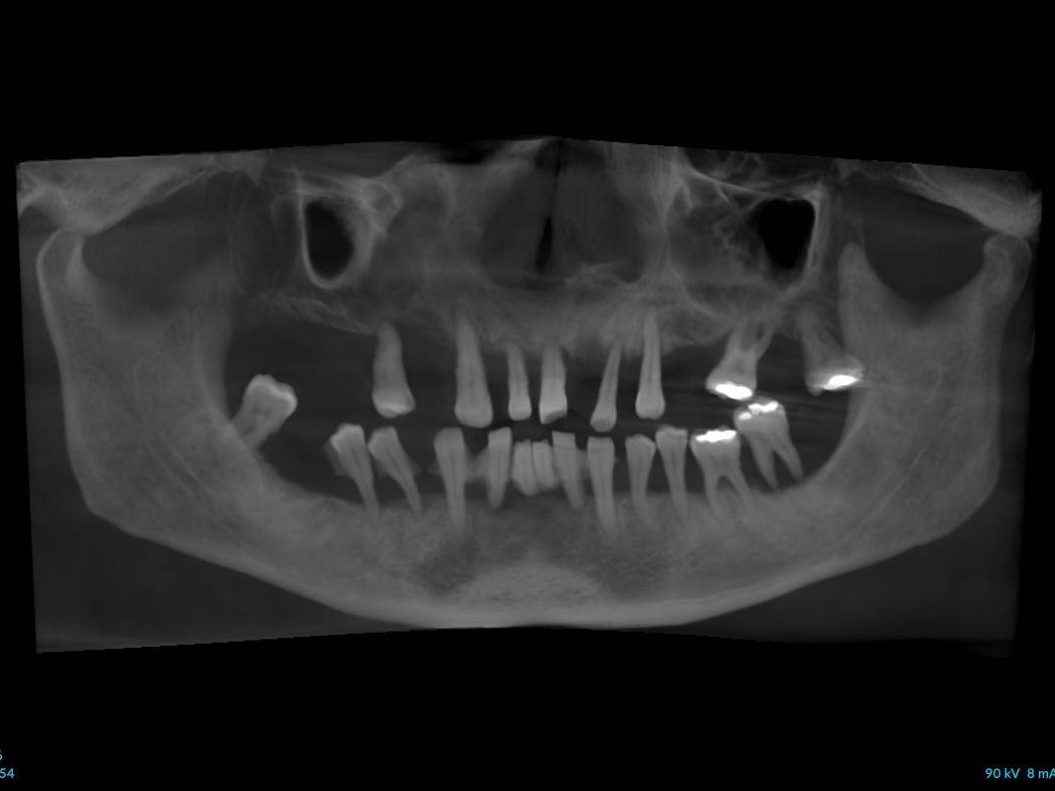

- Radiografia prima dell’intervento